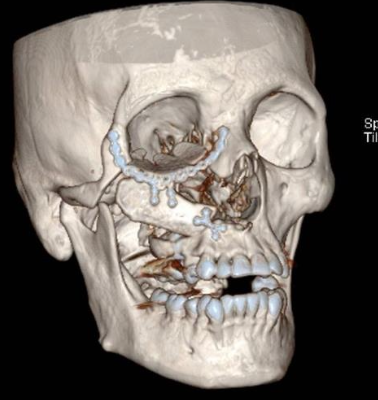

Diego Soto V, Melissa Pavez K, Sebastián Morales Z.

|

|